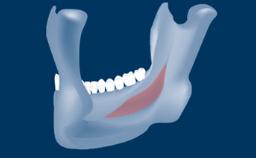

- intraoperative complications of transcrestal sinus floor elevation

- postoperative complications of sinus floor elevation